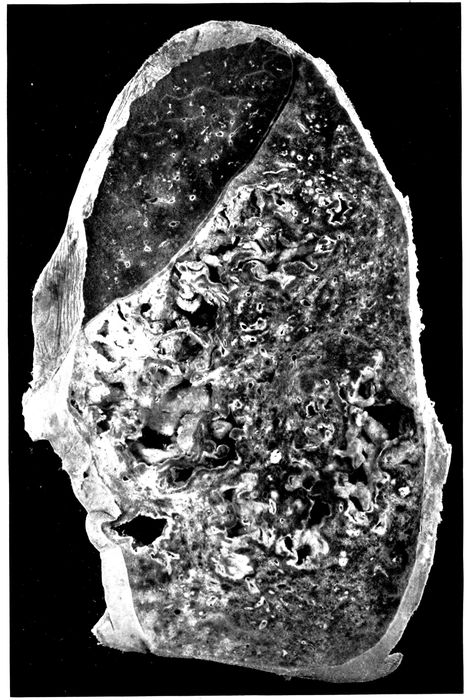

| 7. | Bronchopneumonia with purulent bronchitis and peribronchial hemorrhage | 190 |

| 8. | Streptococcus pneumonia with massive necrosis | 201 |

| 9. | Abscess below pleura with perforation caused by hemolytic streptococci | 202 |

| 10. | Interstitial suppurative pneumonia; interstitial septa are the site of suppuration and lymphatics are distended with purulent fluid; empyema | 211 |

| 11. | Suppurative interstitial pneumonia | 212 |

| 12. | Suppurative interstitial pneumonia | 216 |

| 13. | Suppurative interstitial pneumonia showing a dilated lymphatic | 217 |